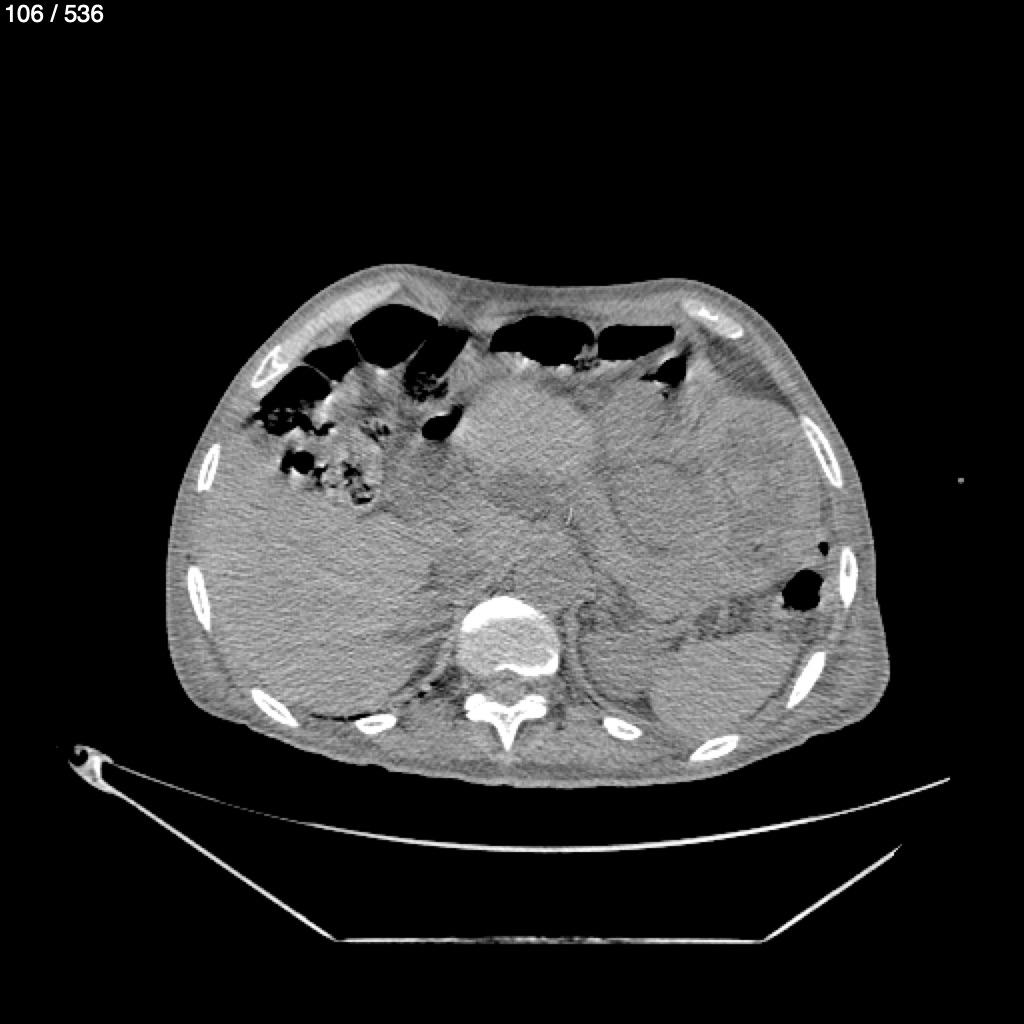

Angel Villalobos Palomeque 73 A - T.C Abdomen Simple